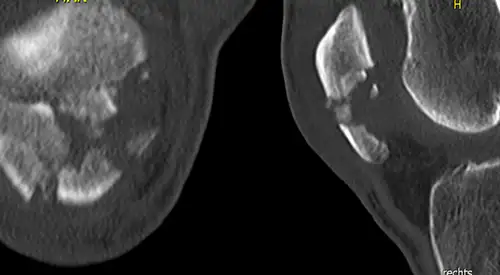

Las radiografías ayudarán a identificar la fractura de rótula.

En ocasiones se requiere la solicitud de pruebas complementarias (resonancia o TAC) para visualizar el estado del cartílago u observar con más detalle la fractura.